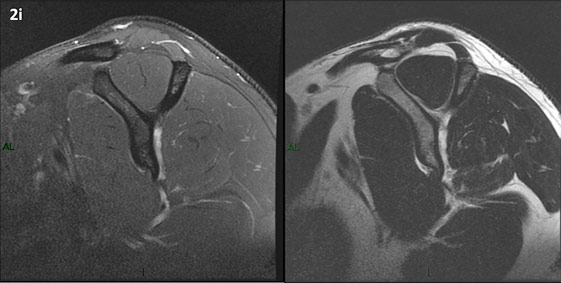

Figura 2 (a-j): Imagens consecutivas de RM no plano sagital nas ponderações T2 com supressão de gordura (DP SG) à esquerda e T2 à direita. Clique na seta para passar as imagens.

Figura 2 (a-j)': Imagens consecutivas de RM no plano sagital nas ponderaçõesT2 com supressão de gordura (DP SG) à esquerda e T2 à direita. Clique na seta para passar as imagens.

Figura 2a’ mostrando os tendões do subescapular (seta rosa), da cabeça longa do bíceps (seta verde), do supraespinhal (seta vermelha), do infraespinhal (seta laranja) e do redondo menor (seta amarela).

Figuras 2b a 2j’: Acompanhando o tendão do redondo menor (seta amarela fina) é possível notar lipossubstituição ao redor da junção miotendínea (setas amarelas grossas) e a atrofia principalmente da porção mais lateral (seta salmão). A porção mais medial (seta branca) tem volume preservado.

Repare que estas alterações também não são evidentes nas imagens com supressão de gordura no plano sagital.

Chafik et al. também relataram a presença de um pequeno nervo motor acessório em número variável que se insere na porção lateral do músculo redondo menor. O nervo acessório, ao contrário do principal, tem um curso reto e extra-fascial, sendo menos vulnerável aos efeitos compressivos. De fato, nos casos da atrofia parcial do redondo menor, é mais frequente a atrofia da porção mediodorsal com preservação da porção lateroventral, o que poderia ser explicada pela presença do ramo acessório mais lateral do nervo axilar, embora atrofia isolada do componente lateroventral tenha sido reportada em cerca de 17% dos casos de atrofia de apenas uma porção, o que pode ter sido causada por lesão do nervo acessório. No caso do paciente deste mês, a atrofia é mais evidente nesta porção mais lateral e ventral do redondo menor.

É importante que o protocolo de ressonância magnética do ombro tenha sequências ponderadas em T1, T2 ou densidade protônica (DP) sem supressão de gordura em pelo menos dois planos, idealmente nos planos coronal e sagital, para a detecção de lipossubstituição que pode passar despercebida nas imagens com supressão de gordura.